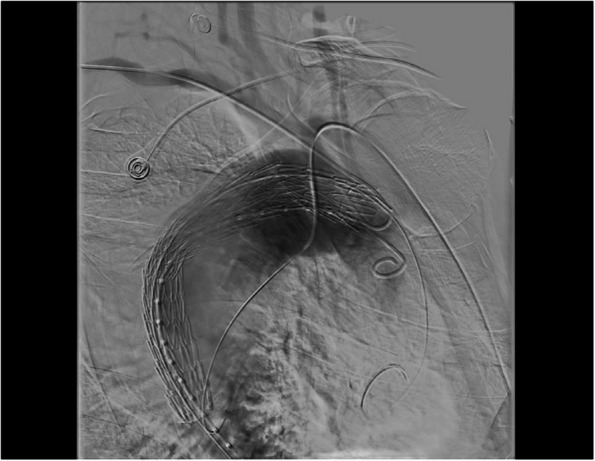

Case presentation: Α 55 year old patient was admitted in our hospital with chest pain. After the initial clinical and laboratory workout that was negative for acute coronary syndrome, Computed Tomography Angiography revealed an aneurysm of the descending aorta 10,3 cm in width, and a right sided aortic arch (Edwards' classification). Endovascular repair was selected as the treatment option of choice. Technically the endografting was challenging, firstly because of the right sided aortic arch, secondly because the four aortic branches originate independently. In order to identify the orifices of arch vessels during the angiography, brachial access in both upper extremities was achieved. In this way, it was possible to correctly deploy the thoracic aortic stent graft. No endoleaks were observed in the final angiography. Postoperative Computed Tomography Angiography 10 months after the operation showed no endoleaks.